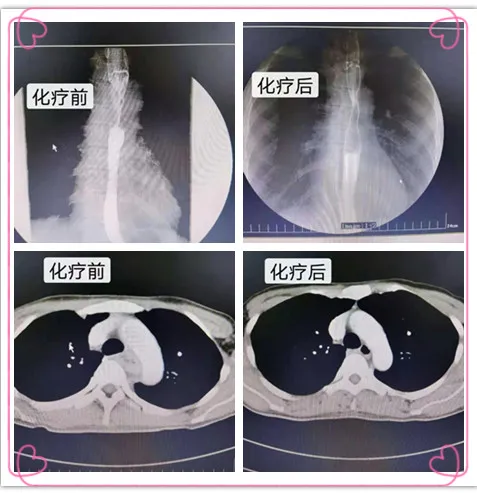

2020年10月,潼南区的李女士吃东西时有明显的吞咽梗阻,无法进食干饭等干硬食物,进食稀饭和饮水也非常困难,身体状况每况愈下,体重迅速下降8公斤,胃镜检查发现是食管癌。年仅41岁的李女士知晓病情后如五雷轰顶,..